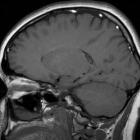

Как правило, всевозможные расстройства регуляции вентиляции легких у человека проявляются из-за различных нарушений функциональности дыхательного центра. Можно обозначить несколько механизмов расстройств дыхательной регуляции, все они связаны с различными отклонениями, которые происходят в афферентной регуляции дыхательного центра и все они сопровождаются развитием апноэ и гиповентиляции. Из-за того, что наблюдается дефицит импульсов, идущих от хеморецепторов, появляются так называемые периодические формы дыхания. Все эти формы представляют собой расстройство дыхательного ритма – наблюдается чередование дыхания и апноэ, то есть, остановки дыхания. Любые расстройства дыхания качественно диагностируются и лечатся здесь: http://m1-privatklinik.ru.

Так называемое дыхание Чейна-Стокса представляет собой постепенное увеличение амплитуда дыхательных движений, которое сменяется его уменьшением и последующим появлением периода апноэ. Эта патология появляется, когда уменьшается чувствительность центрально-мозговых хеморецепторов к углекислому газу. В медицине различаются полное и неполное дыхание Чейна-Стокса.

Дыхание Биота представляет собой чередование одинаковых дыхательных движений и периодов апноэ. Такая патология сопровождает травматические воспалительные поражения мозга, а также опухоли задней части черепа. Здесь имеет значение не только хеморецептивная стимуляция инспираторных нейронов, но и импульсы, которые поступают из парабронхиальных ядер пневмотаксического центра Люмсдена и нейронов ретикулярной формации. Дыхание Биота наблюдается, когда снижается тоническая импульсация, например, это очень часто случается при синдроме асфиксии у новорожденных.